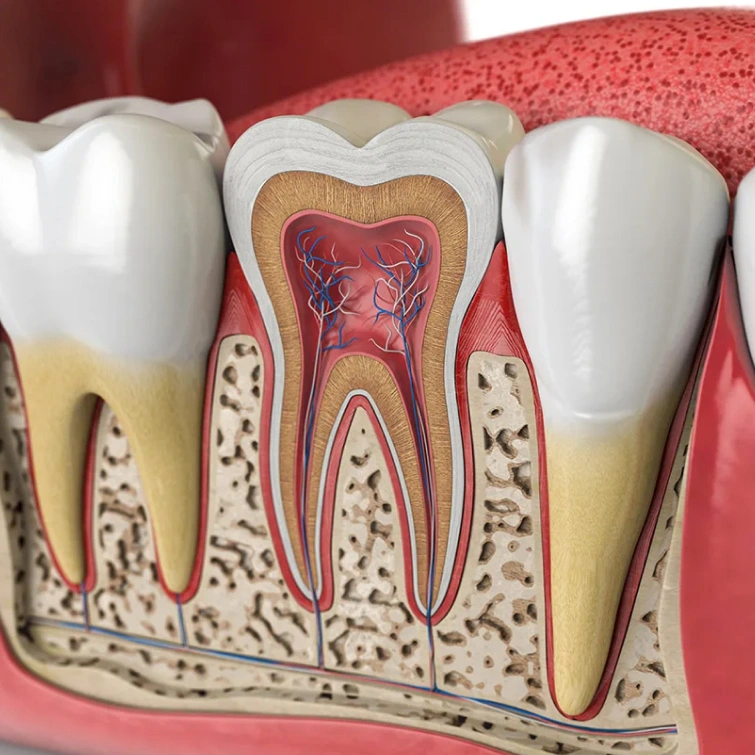

Removing Decay & Infected Pulp

After you are completely numbed and comfortable, your dentist will begin the procedure of extracting decayed or infected material, starting from the outermost layer of enamel and progressing towards the inner pulp. Following the removal of infected pulp, the canals will be thoroughly cleaned and the area will be flushed with a specialized disinfectant to eradicate any residual infection.